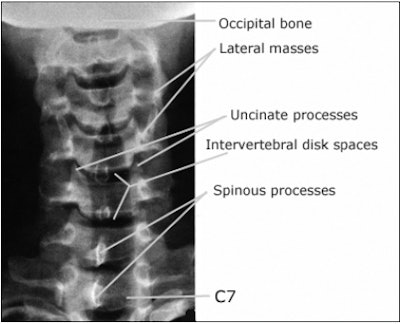

AP axial projection of the cervical spine

On the AP view of the cervical spine the bodies of the C-3 to C-7 vertebrae (in young patients the C-l and C-2 vertebrae may be visible) are well demonstrated, as are the uncovertebral (Luschka) joints, and the intervertebral disk spaces. The spinous processes are seen almost on end, casting oval shadows that resemble teardrops.

An AP axial cervical spine radiograph. Note that this projection demonstrates the C-3 through C-7 vertebral bodies and the intervertebral spaces. The spinous processes are seen superimposed on the bodies resembling teardrops. The C-1 and C-2 vertebrae are not adequately seen. Image courtesy of Dr. Naveed Ahmad.